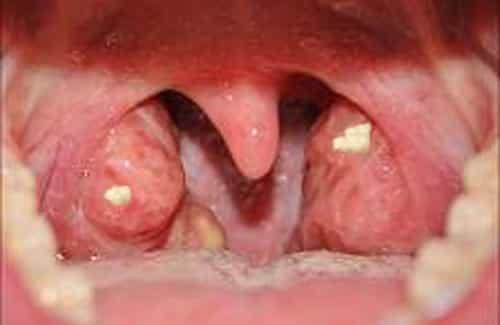

6White Patches on tonsils

Large tonsil stones can be seen with a naked eye. White spots on your tonsils warrant a doctor’s checkup to find out if they are tonsil stones or some other infection like strep throat or tonsillitis. This can be an even more serious infection which is easily treated with antibiotics.

Image Source: alleghanytrees.com